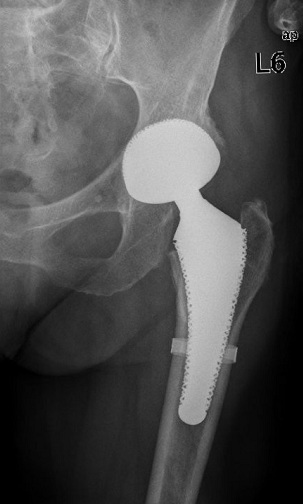

The short stem GHEs in total hip replacement – experience after 380 implantations

• GHEs stem